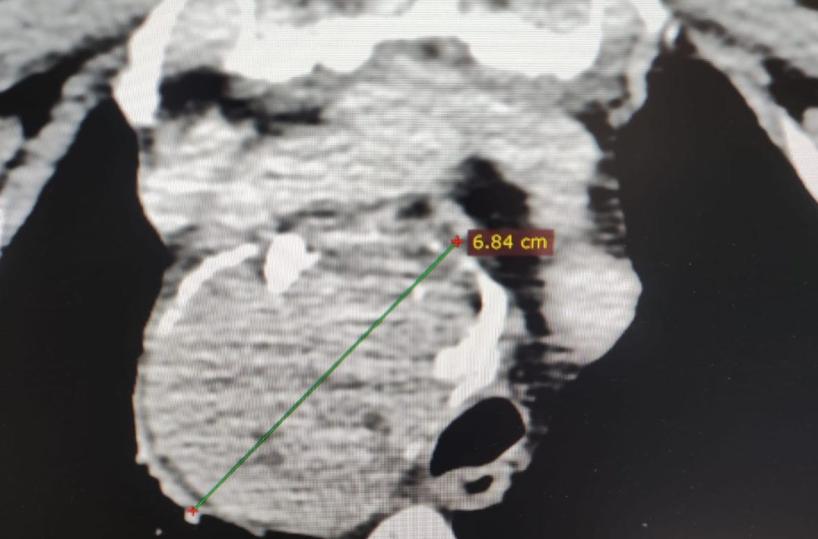

Una complessa tiroidectomia ha permesso di rimuovere con successo un gozzo endotoracico di circa sette centimetri a una donna di 65 anni, al Policlinico di Bari. L’ingrossamento della tiroide, noto come gozzo plongeant, si estendeva nel torace, comprimendo le strutture circostanti e causando una significativa perdita della voce.

La paziente, da circa cinque anni, aveva notato una massa nella parte anteriore del collo e un progressivo calo della voce dovuto alla pressione esercitata dal gozzo sul nervo che controlla le corde vocali. Gli accertamenti radiologici hanno evidenziato che la tiroide, pur spingendo la trachea verso sinistra, non ostruiva il passaggio dell’aria. Inoltre, erano presenti piccoli noduli e calcificazioni.